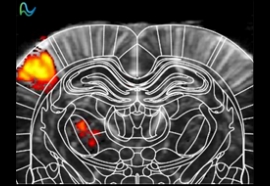

脑功能成像